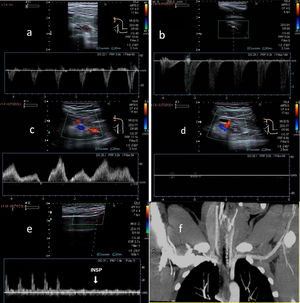

Diagnostic imagingDoppler ultrasound is used to diagnose median arcuate ligament syndrome, revealing a change in the orientation of coeliac trunk in relation to inspiration and expiration (Fig. 6).

A) Hook-shaped coeliac trunk with change in orientation in relation to inspiration and expiration. B) Coeliac trunk with elevation of peak systolic velocities >200 cm/s. C) In expiration, the velocity increases from 192 to 322 cm/s. D) CT angiography: (expiration) focal stenosis of the proximal portion of the coeliac trunk (hooked appearance). E and F (detail): CT angiography (arterial phase) showing the “hair bun and shawl” sign. G) “Hair bun and shawl” sign.

For diagnosis, observation of elevated PSVs in maximum expiration exceeding 200 cm/s with a coeliac trunk-to-aorta ratio greater than 3 is indicative of significant blood flow compromise (Fig. 6B and C).

This technique is very commonly used, especially in evaluating blood vessels in children and adolescents.4 Placing the transducer in B-mode on the axial plane could reveal how the coeliac trunk is compromised and distorted between the abdominal aorta dorsally and the arcuate ligament ventrally.5,7

CT angiography is often necessary to assess the degree of stenosis. Superior pressure against the origin of coeliac trunk, causing it to take on a hooked or J-shaped appearance, is characteristic. Another radiological finding is the “hair bun and shawl” sign, which consists of visualisation on a single axial plane of the compromised, distorted coeliac trunk between the abdominal aorta dorsally and the median arcuate ligament ventrally, which practically surrounds the other two. These findings resemble a head (the aorta) with the hair in a bun (the origin of the coeliac trunk), covered by a shawl (the median arcuate ligament). This enables diagnosis in non-targeted examinations and screening of patients to undergo examinations.8